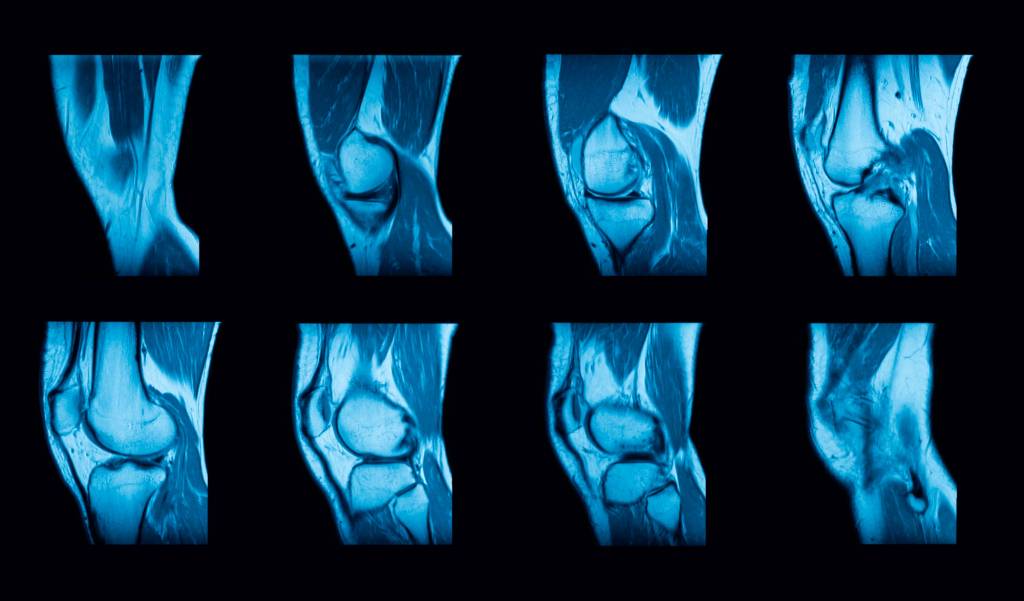

Der Gelenkerguss lässt sich oftmals im Ultraschall gut darstellen. Die Ultraschalluntersuchung wird vor allem eingesetzt an Gelenken, bei denen die üblichen einfachen Tests nicht gut möglich sind (z. B. Hüfte). Eine Röntgenuntersuchung kann einen Gelenkerguss aufdecken. Sogar eine Kernspintomographie (MRT, Magnetresonanztomographie) kann in Frage kommen.